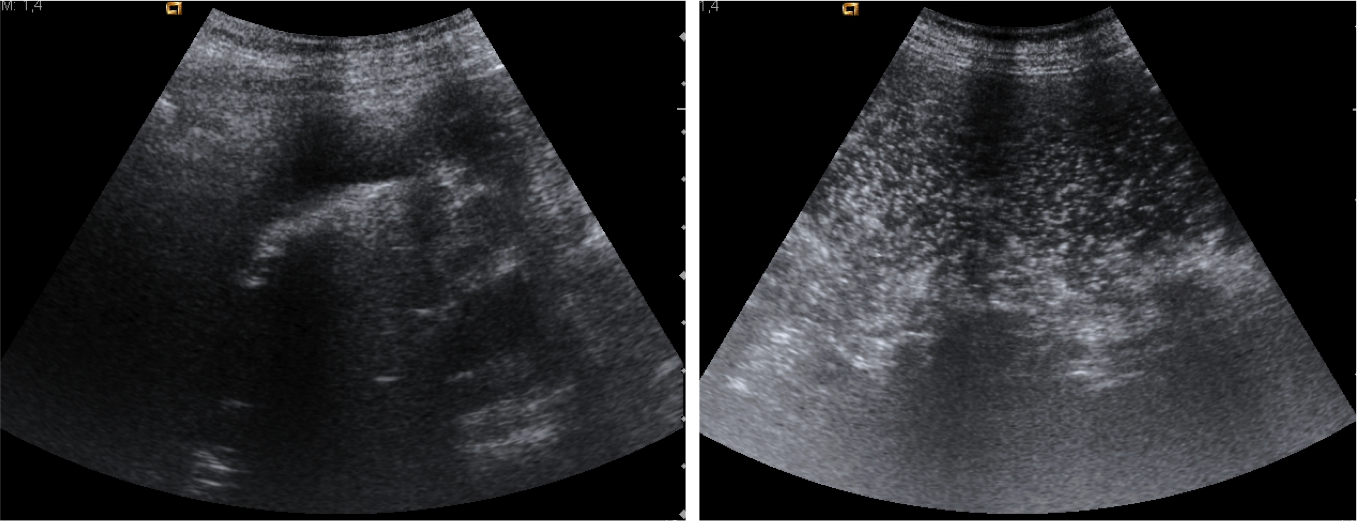

Ecografía:

• Puede detectar la fístula entre la vesícula y el duodeno, litasis residulaes y detectar la obstrucción gástrica.

Ec

Se observan muchos artefactos por el gas existente en duodeno y estómago. En la zona teórica de la vesícula se observa una dudosa imagen hiperecogénica con sombra posterior. A la izquierda la cámara gástrica con abundante contenido en su interior.